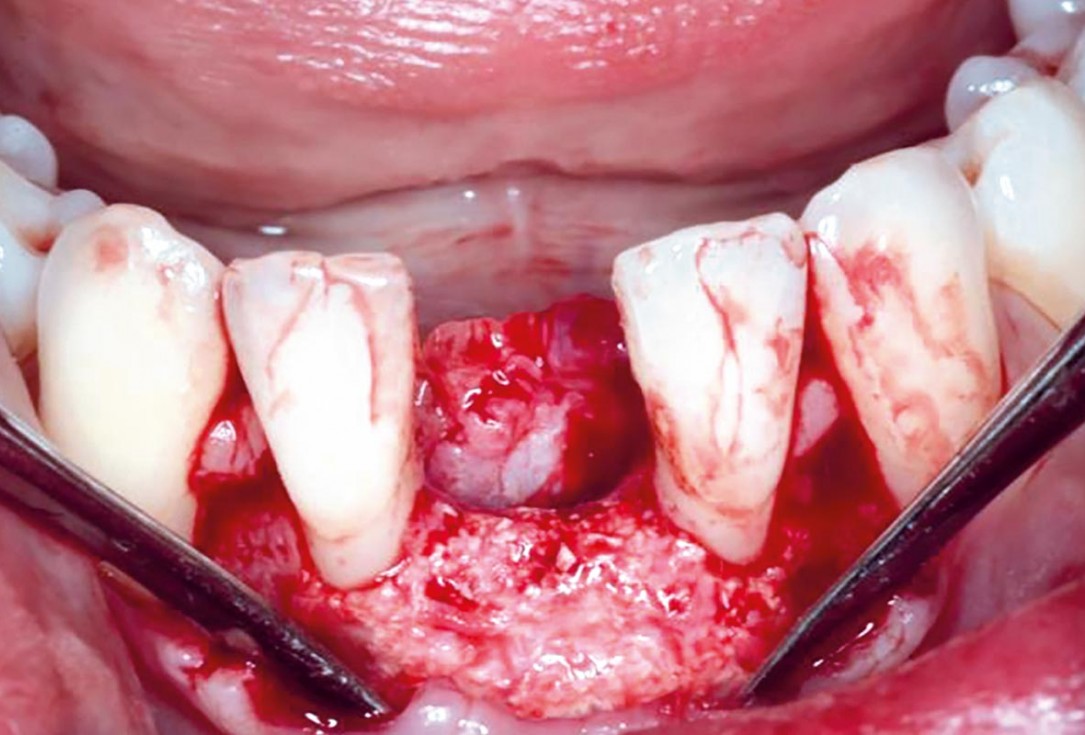

01/12 - Intra-operative view.Horizontal GBR in the anterior mandible - Dr. B. Molnar